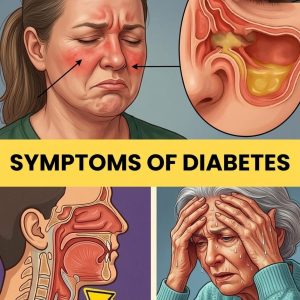

Early symptoms of type 2 diabetes often develop gradually and can be easy to miss. These may include increased thirst, frequent urination, fatigue, blurred vision, slow-healing wounds, and increased hunger. Early screening, healthy lifestyle choices, and medical advice are important for proper diagnosis and management.

Type 2 diabetes is a chronic metabolic condition that often develops gradually and silently, making it difficult to detect in its earliest stages. It is primarily characterized…